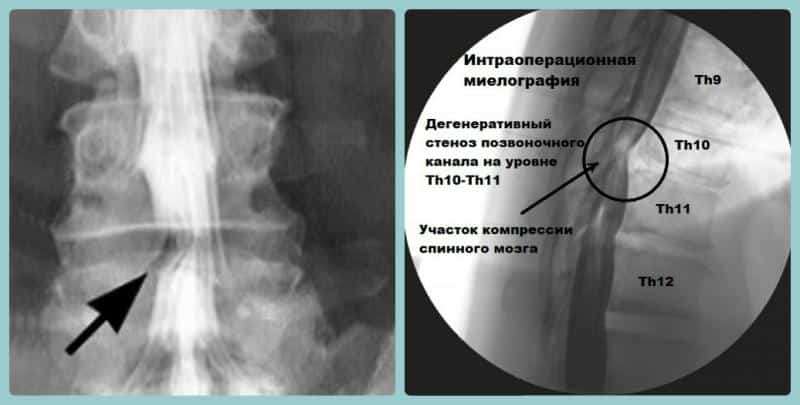

- стеноз позвоночного канала;

- участки компрессии;